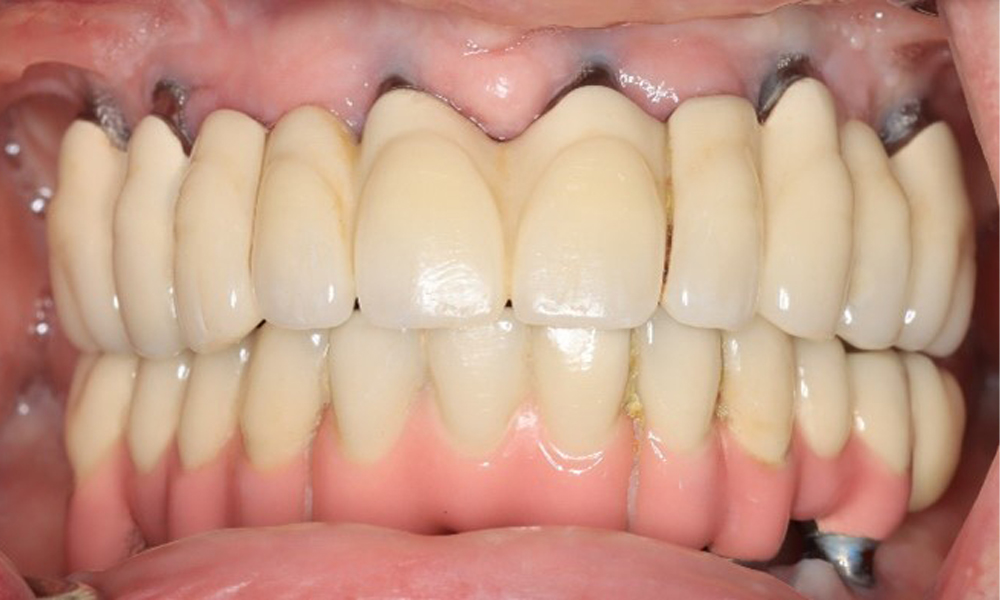

A 74-year-old patient presents for a consultation. The anamnesis shows that the patient has well-controlled hypertension and is taking Lixiana. Additionally, the patient had a kidney carcinoma in 2020. The patient’s lifestyle is unremarkable. She has no natural teeth left and has six implants in both the upper and lower jaws, which are fitted with crowns or bridges. Current findings show no peri-implant mucositis or peri-implantitis; however, there are occasional minor bleeding at the implant sites.

The peri-implant situation is currently stable. Due to the complexity of the superstructures, the patient has a moderate risk of development and a low risk of progression for peri-implant diseases.